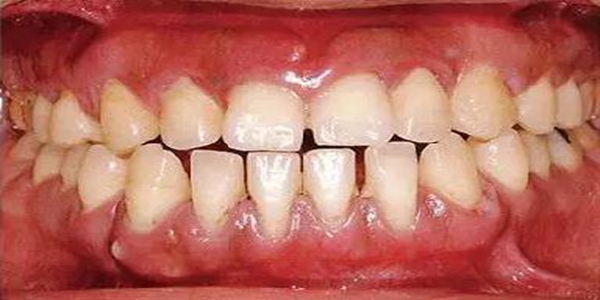

●健康且正常的牙周組織臨床圖像